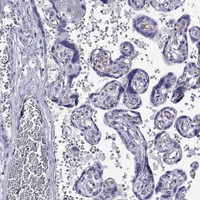

Immunohistochemical staining of human placenta shows moderate membranous positivity in endothelial cells.